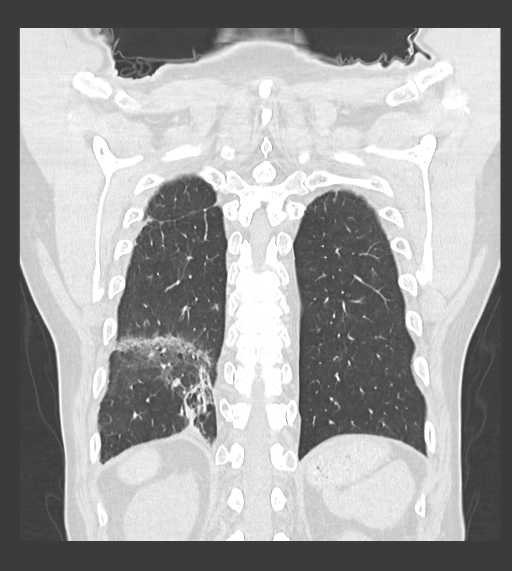

CT検査

内科領域

胸部

肺がん